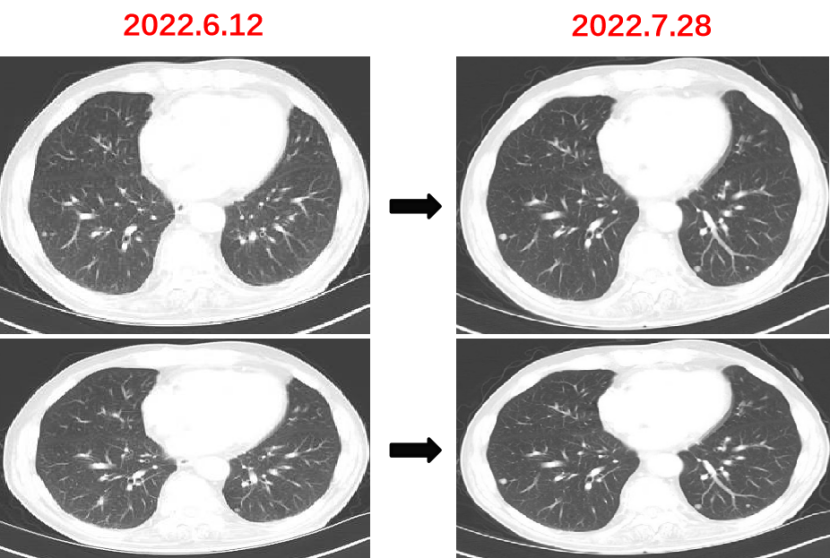

Q1 对于晚期转移性结直肠癌患者,目前,免疫治疗在新辅助治疗中的研究进展和临床应用如何? 结直肠癌是全球第三大肿瘤,转移性结直肠癌的5年生存率只有14%,治疗手段包括手术、化疗、放疗和靶向治疗等。免疫检查点抑制剂的出现也改写诊疗指南。大肠癌dMMR/MSI-H亚型约占所有病例的15%和mCRC病例的5%。由于dMMR/MSI-H的高突变率,肿瘤具有高免疫原性,使其能够激活免疫系统的抗肿瘤作用。 KEYNOTE-177这是一项三期国际开放标签随机对照研究,入选MSI-H/dMMR的IV期结直肠癌患者,比较帕博利珠单抗治疗(200 mg,每3周1次,最多35个周期)与在一线中使用或不使用抗VEGF或抗EGFR单克隆抗体的标准双药化疗,主要终点是PFS和OS。结果显示,帕博利珠单抗组患者的中位PFS时间为16.5个月 VS 8.2个月;3年PFS率分别为42% VS 11%,3年OS率分别为61% VS 50%。帕博利珠单抗组ORR为45.1%(20例完全缓解,49例部分缓解),化疗组为33.1%(6例完全缓解,45例部分缓解);帕博利珠单抗组83.5%的患者至少维持缓解了2年;在化疗组中,只有33.6%的患者缓解持续时间≥2年。KEYNOTE-177研究证实了帕博利珠单抗可以作为MSI-H或dMMR患者的一线标准治疗。 在2021版CSCO结直肠癌诊疗指南中,MSI-H结直肠癌姑息一至三线均推荐免疫治疗,其中帕博利珠单抗作为一线治疗的一级推荐;CheckMate-142研究选择MSI-H/dMMR转移性结直肠癌患者,单免后线vs双免后线vs 双免一线:ORR 39% vs 65% vs 71%,DCR 69% vs 81% vs 84%,一线双免完全缓解率为13%。结果说明双免好于单免,一线好于后线。CheckMate-142研究具有划时代意义,它将免疫治疗从后线前移到一线。 COMMIT研究是一项前瞻随机开放标签的三期临床研究,评估了阿特珠单抗单药治疗对比mFOLFOX6(氟尿嘧啶、奥沙利铂、亚叶酸钙)+贝伐珠单抗+阿特珠单抗一线治疗dMMR或MSI-H转移性结直肠癌的疗效和安全性,目前该试验还在进行中。未来该项研究的结果将回答对于MSI-H晚期结直肠癌,在一线免疫治疗的基础上联合化疗和抗血管靶向药物是否可以进一步提高免疫治疗的疗效。 CheckMate 8HW是另一项随机对照三期临床研究,在一线治疗dMMR或MSI-H转移性结直肠癌中,比较纳武利尤单抗单药、纳武利尤单抗联合伊匹木单抗以及研究者选择的化疗这3种方案的疗效。这项研究将头对头地比较对于MSI-H晚期结直肠癌双免联合是否优于单免的疗效。 Q2 对于MSI-H/dMMR型局部晚期结直肠癌(LACRC),新辅助免疫治疗探索的进展与应用前景如何?有哪些潜在预测疗效的生物标志物? 对于MSI-H/dMMR型局部晚期结直肠癌患者,新辅助免疫治疗可以在肿瘤手术前,提前使患者的免疫系统识别肿瘤细胞,从而使患者的免疫系统更好地产生免疫应答。目前结直肠癌新辅助治疗的探索均为二期研究,探索模式多为双免疫或免疫联合化疗方案,直肠癌多为免疫联合放化疗(同步或序贯)的模式。 NICHE研究是探索纳武利尤单抗联合伊匹木单抗用于Ⅰ-Ⅲ期结肠癌新辅助治疗的二期临床研究,研究共纳入40例结肠癌患者,其中21例为dMMR,20例为pMMR(1例患者同时为pMMR和dMMR),81%的dMMR患者和40%的pMMR患者为临床Ⅲ期结肠癌。患者在接受首次免疫治疗后不迟于6周内接受结肠癌手术,dMMR结肠癌缓解率100%,其中完全缓解的患者占60%,MPR为95%;pMMR治疗组27%的患者也对免疫治疗产生了良好的应答。 NICHE2研究,纳入更多患者,探寻非转移性dMMR结直肠癌患者双免治疗(伊匹木单抗+纳武利尤单抗)的疗效,主要终点为安全性,3年无病生存期。结果显示:MPR率95%,PCR率67%,中位随访13.1个月后没有患者出现疾病复发,毒性可耐受。 NCT04165772研究(前瞻性,单臂,Ⅱ期研究),Ⅱ期和Ⅲ期患者接受新辅助dostarlimab(多塔利单抗)共6个月,结果显示CCR率为100%。 PICC研究是特瑞普利单抗联合或不联合塞莱昔布新辅助治疗错配修复蛋白缺陷或微卫星高度不稳定的局部进展期结直肠癌的双臂随机Ⅱ期临床试验,结果显示完全缓解率高达88%,进一步表明dMMR结直肠癌免疫疗效惊人,潜在替代放化疗及手术。 对于MSI-H或dMMR结直肠癌,NCCN结直肠癌指南中,新辅助治疗增加纳武利尤单抗±伊匹木单抗或帕博利珠单抗单药方案;转化治疗可以选择双免疫或单免疫用药方案。 但并非所有患者都能从免疫治疗中获益,故筛选免疫治疗的疗效预测生物标志物将显得尤为重要。近年来研究主要集中在包括MSI-H、PD-L1过表达、TMB-H(TPS3645)、POLE或POLD1基因突变、PI3K/AKT/mTOR通路、新抗原(身份和数量)、免疫系统状态(免疫细胞特征、T细胞受体相关)等。 Q3 您如何看待对于临床中MSI-H/dMMR 转移性结直肠癌患者使用免疫治疗,部分患者仍然会出现耐药问题? Q4 晚期结直肠癌通常预后相对较差、患者生存期不长,依然是我国困扰结直肠肿瘤治疗的瓶颈问题,但有治愈的可能,此时临床医生制定正确合理用药方案尤为重要。今年上半年发布的CACA-RC指南推荐不适合强烈治疗患者应用曲氟尿苷替匹嘧啶片(TAS-102)联合贝伐珠单抗,作为晚期不可切除结直肠癌姑息一线治疗方案。请您谈谈该推荐治疗对我国晚期不可切除结直肠癌患者的临床治疗带来怎样的获益? 今年上半年CACA-RC指南推荐了不适合强烈治疗的患者应用TAS-102联合贝伐珠单抗作为不可切结直肠癌一线治疗方案,是在不可切除晚期结直肠癌一线治疗中石破天惊的一项突破。晚期mCRC的标准化疗方案在指南中是以奥沙利铂或伊立替康为基础的FOLFOX和FOLFIRI方案,在此基础上,可以根据基因分型联合西妥昔单抗或者贝伐珠单抗,但是依旧有部分患者身体状况无法耐受加强化疗,针对这一类患者的治疗方案选择非常有限,且预后情况并不理想。TAS-102+贝伐珠单抗治疗方案毒副反应相对较低,(临床试验提示比贝伐珠单抗联合卡培他滨效果好)疗效确切,在未来较长一段时间内,尤其是目前疫情肆虐,患者不方便住院治疗时,TAS-102可作为国内不适合强烈治疗的mCRC患者及老年患者的一线治疗优选方案,并为患者带来持续的、更优的生存获益。 二 病例分享 专家简介 王峰 教授 医学博士,副主任医师,硕士研究生导师 滨州医学院附属医院肿瘤科副主任 澳大利亚悉尼维斯迈医学中心访问学者 中华医学会放射肿瘤治疗学分会骨与软组织学组委员 中国临床肿瘤学会(CSCO)神经系统肿瘤专家委员会委员 山东省医师协会肿瘤精准医疗医师分会常务委员 山东省医师协会肿瘤放疗医师分会委员 山东省抗癌协会消化道肿瘤分会常务委员 山东省医学会咽喉肿瘤多学科联合委员会委员 山东省医学会烟草病学与戒烟多学科联合委员会委员 山东省健康管理协会消化道肿瘤防治分会常务委员 山东省医学会放射肿瘤学分会青年委员 山东省医学会妇科肿瘤多学科联合委员会委员 滨州市医学会放射肿瘤学专业委员会副主任委员 01 基本情况 (一)基本信息 患者男性,65岁,于2021-08-26第一次入滨州医学院附属医院风湿免疫科。 主诉:发作性右踝关节肿痛3年,再发1月。 查体:双足第一跖趾关节可见红肿,伴局部皮温升高。 既往史、个人史:既往脑梗死病史7年余,未遗留后遗症;有“膀胱结石”病史1年余,未系统诊治;有“痛风性关节炎”3年余,曾于滨州医学院附属医院风湿免疫科治疗。有高血压病史10年余,最高血压180/110mmHg,口服“吲达帕胺片”,血压控制可。 常规检查发现2次大便潜血阳性。 (二)辅助检查结果 1.肠镜检查 直肠、乙状结肠:直肠距肛门7cm可见一巨大溃疡型病变,表面溃烂,污秽苔,周边环堤样隆起,累及管腔1/3周圈,管腔无狭窄,于病变周边多点活检8块,质脆易出血;乙状结肠见一0.5cm*0.3cm息肉,余黏膜光滑,皱襞清晰,蠕动规律;肛管未见异常。降结肠、横结肠:横结肠见一0.3cm*0.4cm 0-IIa型息肉,表面粗糙,余黏膜光滑,血管纹理清晰,未见异常。 诊断:1.直肠Ca(进展期 溃疡型);2.结肠多发息肉——内镜下冷切除术+息肉摘除术。 2.胸部、上腹部未见明显异常。 直肠MR增强+DWI:直肠距肛缘约5.5cm处肠壁明显不均匀增厚,累及长度约6.0cm,呈等/长T1、等/稍长T2信号,T2压脂呈不均匀高信号,DWI呈高信号,ADC图信号减低,增强扫描呈明显不均匀强化,相应局部管腔狭窄,邻近浆膜面模糊,周缘可见小淋巴结。 02 治疗经过 2021-09-08:于全麻下行全直肠系膜切除+末端回肠预防造瘘术。 术中见:肝脏、胃、腹壁等无转移性结节。肿块位于腹膜返折处,活动度差,侵及浆膜。肠周见明显散在肿大淋巴结。 术后病理:直肠下段中分化腺癌,侵犯外膜下脂肪组织,肿瘤出芽分级(高级别,Bd3),侵犯神经侵犯,未见确切脉管内癌栓;两侧手术切缘、环周切缘及标记切缘内均未查见癌累及,肠周淋巴结内未查见转移癌(0/17)。pTNM分期:pT3N0Mx。免疫组化结果:CK(+),MSH2(+),MSH6(+),MLH1(+),PMS2(+),MDR-1(3+),HER2(3+),P53(3+),Ki-67阳性率约70%。 术后诊断: 1.直肠癌II(pT3NOMO)期术后; 2.结肠多发息肉术后; 3.痛风性关节炎; 4.高血压病(3级 很高危); 5.脑梗死。 CSCO指南: 2021-10-04至2022-06-03:FOLFOX方案化疗10周期(奥沙利铂150mg d1+氟尿嘧啶 0.7g d1+4.4g civ);术后预防性放射治疗DT5000cGy/25f,同步卡培他滨。 2021-11-25至2021-12-06:尿培养提示肺炎克雷伯菌感染,结合泌尿外科、感染科会诊意见,给予左氧氟沙星抗感染治疗。 2022-06-12 肺无法穿刺活检。 基因检测示:(直肠)KRAS/BRAF/NRAS/PIK3CA 基因均未检出突变。伊立替康UGT1A1基因检测结果:非风险基因型。 CSCO指南: 2022-06-20:西妥昔单抗联合FOLFIRI方案治疗(西妥昔单抗900mg d1,伊立替康320mg d1,氟尿嘧啶0.7g iv 4.3g civ)。 2022-07-06:骨髓抑制、腹泻,西妥昔单抗联合FOLFIRI方案治疗(西妥昔单抗900mg d1,伊立替康280mg d1,氟尿嘧啶0.7g iv 4.3g civ)。 疗效对比: 循证依据: C-TASK FORCE研究:首个证实TAS-102联合贝伐珠单抗治疗mCRC的疗效及安全性研究。TAS-102联合贝伐珠单抗是难治性mCRC患者潜在治疗选择,更多临床获益有待进一步研究。 TAS-102联合贝伐珠单抗治疗mPFS时间和mOS时间分别为5.6个月和11.2个月。 TAS-102联合贝伐珠单抗不良反应主要为血液学毒性。 日本大样本RWS:TAS-102和瑞戈非尼不同排序的回顾性研究。 日本大样本RWS:TAS-102单药较瑞戈非尼单药,可显著延长mOS,降低AE。 日本大样本RWS:两药序贯疗效优于单药,且≥65岁先用TAS-102获益更显著。 日本大样本RWS:TAS-102序贯瑞戈非尼组持续治疗时间更长。 2022-07-27至今 给予贝伐珠单抗联合TAS-102治疗期间复查CT评估SD,胃肠道反应不重,骨髓抑制Ⅰ度,耐受性尚可。 *本文仅代表专家观点,并经专家审校。